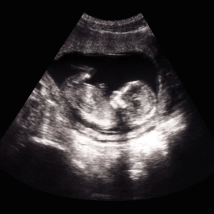

Written and reviewed by medical experts who come from and work with many different communities in California

Informed by patients and families who faced the same medical conditions